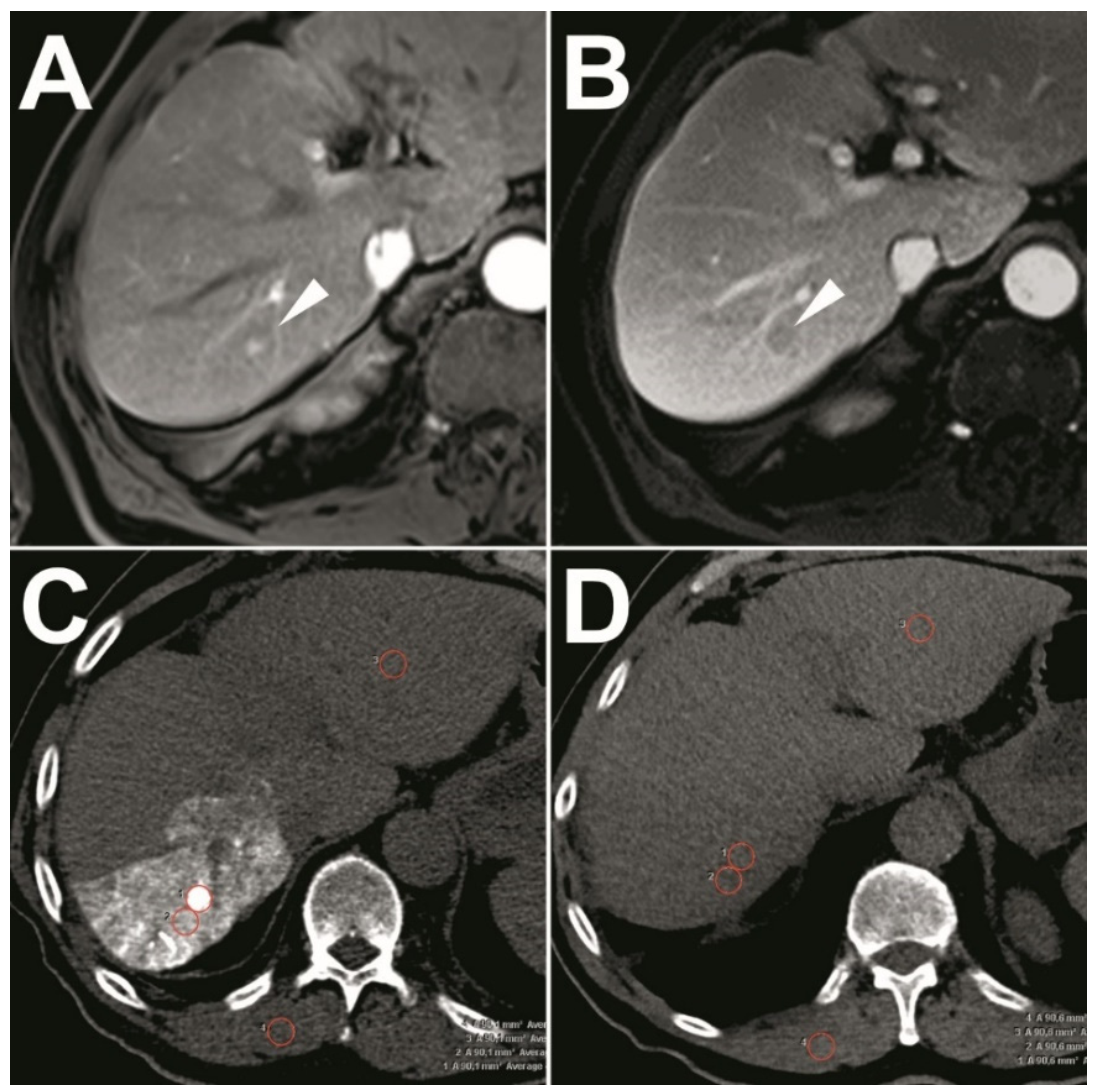

2.2. Pre-Interventional Imaging

2.5. Radiological Follow-Up

3.2. Success of Ethiodized Oil Tumor Marking

3.3. Quantitative Analysis of the Visualization of Target-HCCs

3.4. Success of IRE

3.5. Adverse Events and Follow-Up